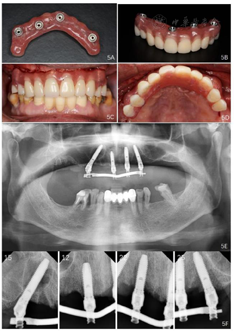

面像;E:佩戴后曲面体层片;F:戴牙后根尖片(3)制作终义齿:种植一期手术6个月后,制作钛支架丙烯酸树脂固定义齿,完成终义齿固定修复。

治疗结果:上颌即刻固定义齿试戴,义齿被动就位顺利,咬合关系恢复至第二前磨牙,义齿螺丝加力至15Ncm。检查患者前牙区覆

覆盖关系恢复正常,唇侧丰满度良好,双侧后牙区咬合关系稳定(图5,图6),患者满意。

即刻修复6个月后佩戴上颌终义齿,咬合关系恢复至第一磨牙,4颗种植体螺丝被动就位后分别加力至15Ncm。口内检查:中线、义齿边缘交界线、义齿切缘曲线、

平面、覆

覆盖关系、双侧磨牙咬合关系均良好(图7,图8,图9)。